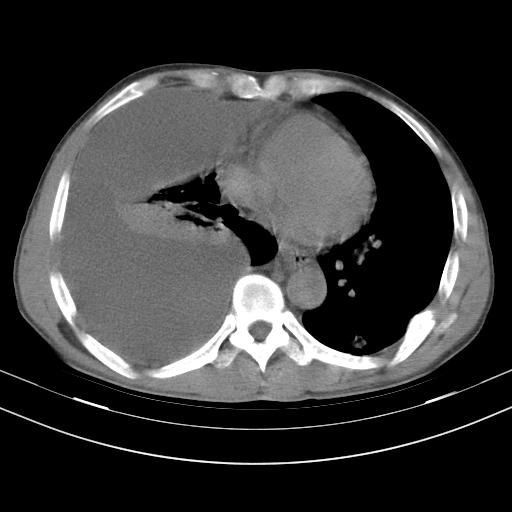

男性,44岁,结核病史多年。现胸闷气短,咳嗽,偶咳血。

右侧胸腔积液

右肺下叶不张

双肺多发结节影最分空洞形成考虑占位不除外结核

双肺陈旧性病变

1、右侧大量胸腔积液伴右肺压缩性膨胀不全,建议抽液治疗后复查 2、两肺继发性tb伴空洞形成。

1)两肺继发性肺结核伴空洞形成,左肺多发性结核球。2)右侧大量胸腔积液伴右肺部分膨胀不全。3)纵隔淋巴结肿大。

吉大一院胸水抽检结果:结核性胸水